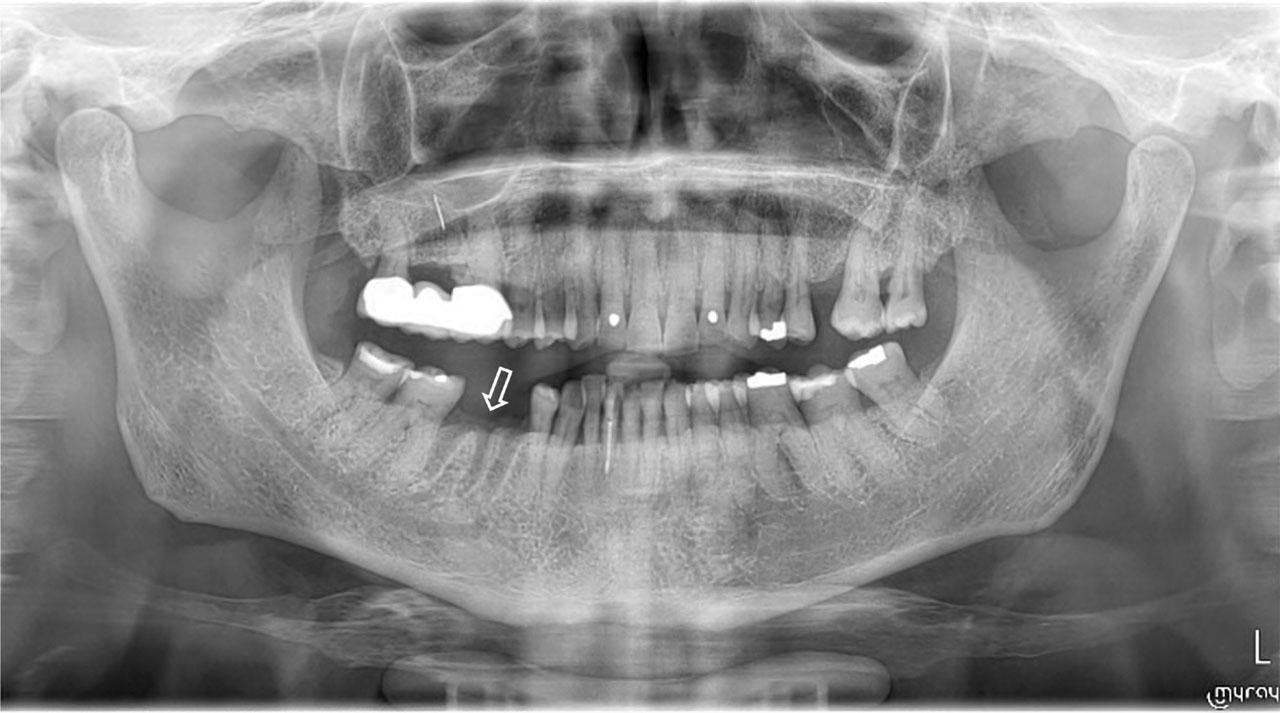

Figure 3:

Panoramic radiograph of a cancer patient, who received antiresorptives and presented with a non-healing socket (phantom socket) two months after the dental extraction of the mandibular molar tooth. Patient was diagnosed with MRONJ stage 2.